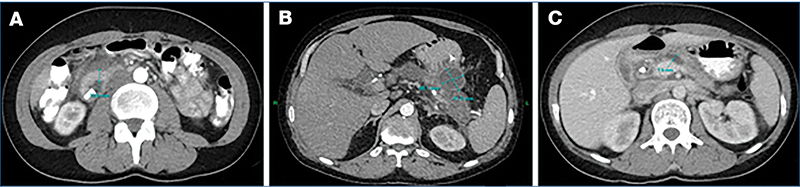

MRI-vizsgálat csupán egy esetben állt rendelkezésre (4. ábra), amely során a pancreas 10–13 mm vastagságúnak imponált, a Wirsung-vezeték teljes hosszában tágult, a duodenum falának megvastagodása pedig szintén megfigyelhető volt. Vizsgálataink során az ultrahang (UH) és a komputertomográfia (CT) bizonyultak a leginformatívabb képalkotó eljárásoknak (1. táblázat); ezek szolgáltatták a legtöbb releváns morfológiai információt a diagnosztikai döntéshozatalhoz (5. és 6. ábra).

(A) Megvastagodott falú duodenum (12 mm); (B) A gyomor és a pancreas teste között elhelyezkedő ciszta (36×41mm); (C) Tágult Wirsung-vezeték (7 mm)

(A) A pancreastestben egy 18 mm nagyságú cystosus képlet látszik; (B) A Wirsung-vezeték egyenetlenül 4 mm tág